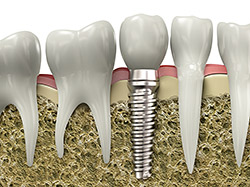

An implant is a synthetic tooth root in the shape of a post that is surgically placed into the jawbone. The “root” is usually made of titanium, the same material used in many replacement hips and knees, and a metal that is well-suited to pairing with human bone. A replacement tooth is then fixed to the post. The tooth can be either permanently attached or removable. Permanent teeth are more stable and feel more like natural teeth.

Implants are versatile. If you are only missing one tooth, one implant plus one replacement tooth will do the trick. If you are missing several teeth in a row, a few strategically placed implants can support a permanent bridge (a set of replacement teeth). Similarly, if you have lost all of your teeth, a full bridge or full denture can be permanently fixed in your mouth with a strategic number of implants.